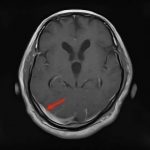

断層撮影

手術前2